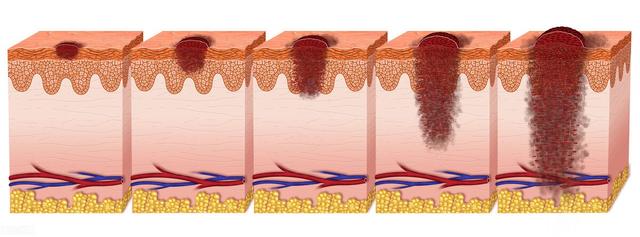

接合母斑→黒色腫

接合部母斑は、手のひら、足の裏、外陰部などの摩擦を受けやすい部位に生じやすい。がんの可能性は他のほくろに比べて高い。

ほくろの形が不規則で、境界がぼやけ、色の濃淡があり、ハレーションを起こしたり、徐々に大きくなり、皮膚がわずかに膨らんだり、厚くなったりしていることがわかったら、すぐに医師に相談する必要がある。どうしてもほくろを切る必要がある場合は、普通の病院の皮膚科か形成外科に行かなければならない。第一に、メラノーマの状態を遅らせる可能性があること、第二に、治療が不完全だと再発しやすいこと、やり過ぎると傷跡が残りやすいこと、などである。

モル数の推移

人間のがん細胞は、もともとは正常な細胞であり、遵法精神に富む「善人」であるが、さまざまながん原因因子の作用により、「悪人」へと疎外されてしまった。 本来、私たちの身体の免疫システムは、人間社会の監視器官のように、これらの「悪人」を的確に狙撃できる強力な免疫監視の役割を担っているが、一部のがん細胞は非常に狡猾であり、さまざまなメカニズムによって、免疫システムの監視と排除からうまく逃れている。本来、私たちの身体の免疫システムは、人間社会における監視器官のように、これらの「悪人」を的確に狙撃できる強力な免疫監視の役割を担っているが、一部のガン細胞は非常に狡猾で、免疫脱走と呼ばれる様々なメカニズムによって、免疫システムの監視・駆除からうまく逃れ、牢獄からの脱獄に成功し、その結果、遺伝子レベルから生体の制御が効かなくなり、無秩序な成長・繁殖を引き起こし、ガンの発生を誘発する。無秩序な増殖と生殖の過程で、血管新生、クローン性の異常増殖を誘発し、正常な細胞の栄養を略奪し、正常な組織を破壊し、"殺人・放火魔 "へと変貌を遂げ、最終的に患者の生命を危険にさらしたのである。善人」と「ヤクザ」の中間段階が前がんである。下の写真はがん細胞である。

- 接合母斑は悪性黒色腫の前癌病変である。境界が明瞭で表面が滑らかな、褐色または黒色の斑状の発疹を呈する。接合母斑は、表皮と真皮の接合部における母斑細胞の活動を特徴とする。手のひらや足の裏など、摩擦や刺激にさらされることの多い部位にできると、がんのリスクが高くなります。多くの人が接合母斑を持っていますが、母斑が急に大きくなったり、色が濃くなったり、表面が崩れたり、もとの毛がなくなったりしたら、がん化する可能性があるので注意が必要です。現在のところ、そのリスクはほくろを繰り返しこすったり、針を刺したり、電気メスで焼いたり、光を当てたり、薬物で侵食したりすると、がんの引き金になる可能性がある。